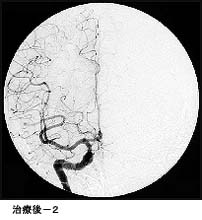

(2)脳動静脈奇形に対する液体塞栓物質を用いた治療

*治療により異常血管は閉塞されました。